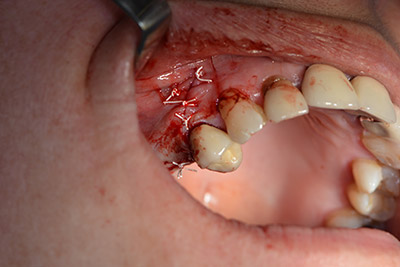

Използвана е абсорбираща мембрана като бариера на букалната страна и покритие на аугментацията. Накрая са поставени устойчиви на слюнка конци (Фиг. 15 до 19).

Закриване на ламбото с устойчиви на слюнка конци

Снимка 19